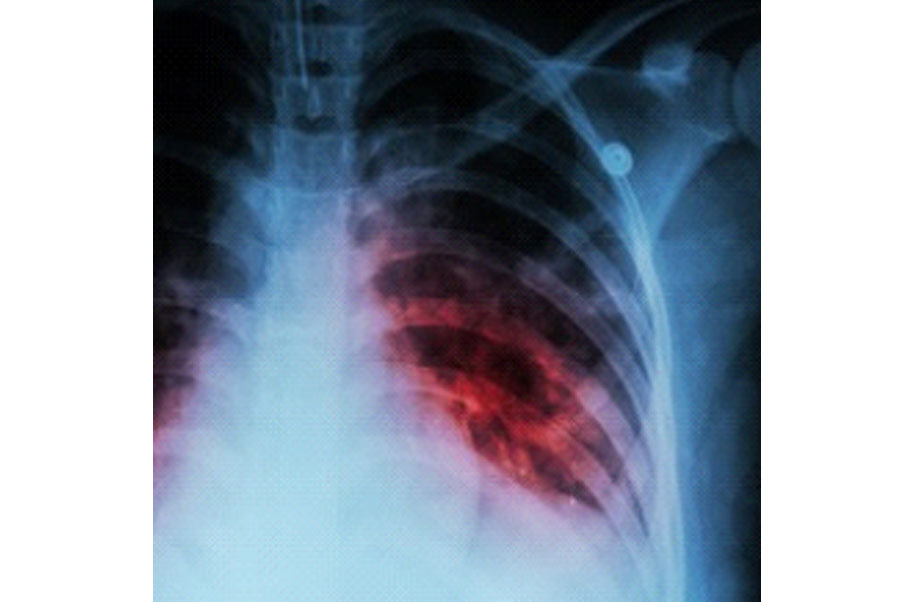

Tuberculosis

A highly contagious infection caused by the bacterium called mycobacterium tuberculosis. Abbreviated tb.

Pain areas: in the chest, pain circumstances: can occur while breathing, cough: can be chronic or with blood, whole body: fatigue, fever, loss of appetite, malaise, night sweats, or sweating, also common: loss of muscle, phlegm, severe unintentional weight loss, shortness of breath, or swollen lymph nodes